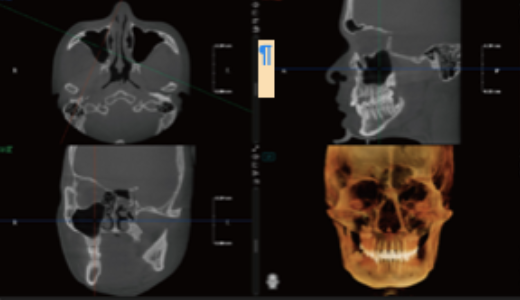

Modo maxilofacial

Modo maxilar y dental

Método de dentición

Modo dientes

Modo Endo

Aquisição completa do paciente para planeamento de implantes em apenas 7 segundos

Ultra-clear display of the entire dental arch and jawbone structure.